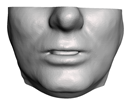

2.5.2. Soft Tissue

2.6. Textured Output Visualization

- Chin. Overall, the amount of error at the chin area is very low. This could be explained by the fact that the skin at the chin is very thin, and the coupling to the mandible makes the simulation highly predictive.

- Lips. In other regions, such as the lips, skin slides strongly over the underlying bones and teeth, and the deformation result is more difficult to predict. Overall, we observe higher variability in the error at the lips, and also some patients with higher error.

- Nose. The quality of the prediction of the deformation of the nose varies strongly across patients. In this case, the variability may depend on the type of surgery performed on each patient’s anterior nasal spine. This type of surgery is not easy to identify in the post-operative CBCT image due to the presence of bone grafts or fixation plates.

- Neck. Finally, we observe large error in the neck area (e.g., patients M5 and M8), and specifically at the junction point between the submental area and the neck (“C point” or “cervical point” in cephalometric analysis). This error was accounted for in our quantitative analysis, which negatively biased the overall results. However, this area is not of special interest to orthognathic surgeons. The deformation is known to be produced by a retraction of skin after surgery, but surgeons do not account for this effect during pre-operative planning.